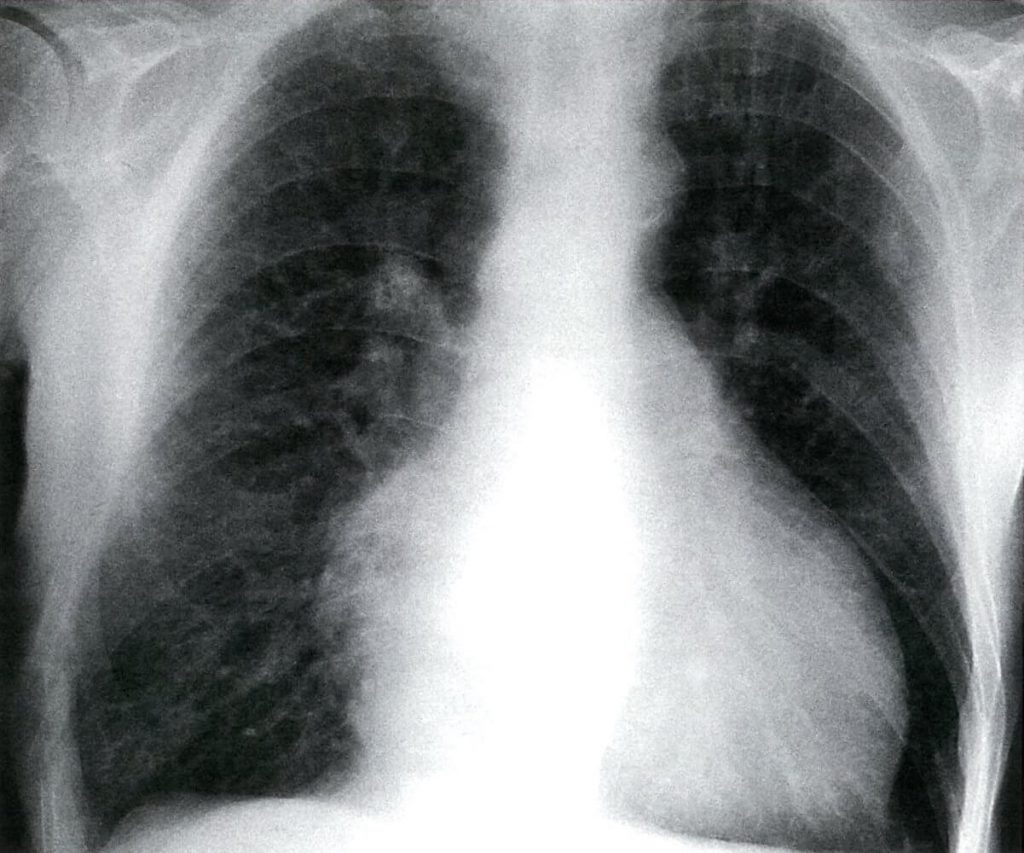

ادم عبارت است از تجمع غیرطبیعیِ مایعات در فضای بین بافتی که به علل مختلفی میتواند رخ دهد؛ مثلاً احتباس مایعات در بدن یا واکنش موضعی به تروما و آلرژی. ادم ممکن است که با تورم اندامها (ادم محیطی) یا تجمع مایعات در حفرهها و اندامهای داخلی (مثلاً ادم ریوی، افیوژن پلور) خود را نشان دهد.